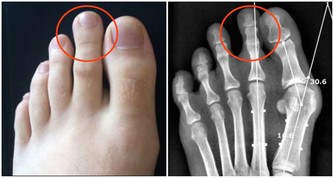

當人體遇冷時,血管收縮,血流速度減慢,血液中輸送的人體所需的各種養料和氧氣就會減少,而膝關節支撐人的身體,本身周圍血管少,血流速度就差,若穿著短褲、短裙則會使膝關節暴露在低溫環境,膝關節長時間受寒涼刺激,血液循環更慢,更易出現水腫和炎症改變,導致滑囊炎、滑膜炎等關節性疾病。